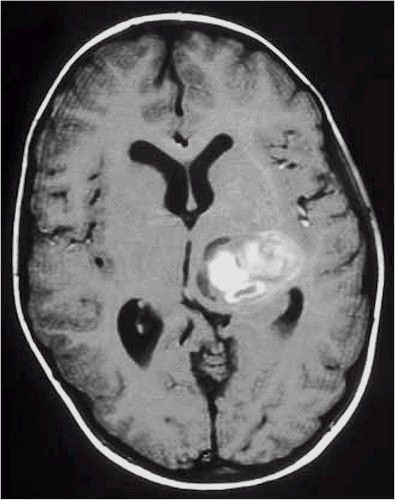

Lesioni caratterizzate da un accrescimento veloce con infiltrazione del tessuto cerebrale attiguo e diffusione a distanza di cellule maligne.

Scopo della chirurgia è ridurre macroscopicamente la massa tumorale per facilitare ulteriori trattamenti (principalmente radio - chemioterapia mentre altri protocolli terapeutici sono ancora in fase di studio).

In queste lesioni la loro conformazione anatomica, praticamente sempre di tipo II (Daumas-Duport) non ha un ruolo così dirimente nell'indicazione chirurgica poiché il comportamento biologico è sicuramente il fattore più importante.

RM:

glioma con segni di trasformazione maligna